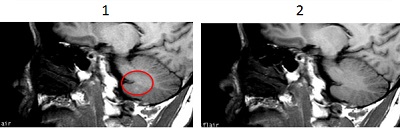

Figure 2. T1 FLAIR Spin Echo brain comparison

Table 2. Image legend

NumberDescription

1T1 FLAIR brain

2Spin Echo brain